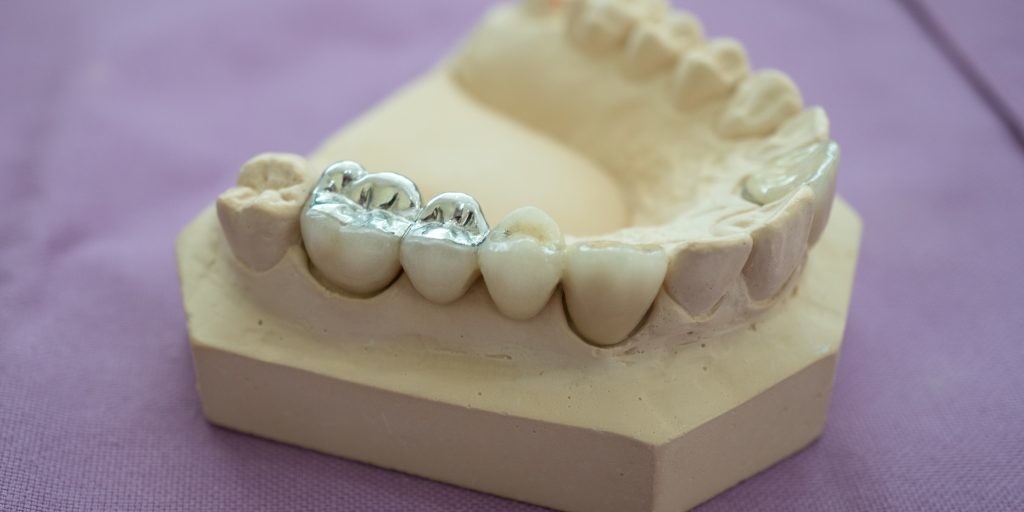

All you need to know about dental fillings

A tooth filling is where material (such as porcelain inlay/onlay or composite) is inserted into a damaged or decayed tooth to restore its original shape and function. This can be either a dental inlay (fills centre of tooth) or onlay (more extensive than an inlay and can cover up to the entire biting surface of a tooth).

Types of fillings

Porcelain fillings – inlay/onlay are tooth coloured and are created to match the current aesthetics of teeth. A porcelain filling is virtually indistinguishable from other healthy teeth and can last up to 20 years.

Composite fillings are similar to porcelain fillings; however, they can last 5-10 years when applied to teeth.

Gold fillings need to be created in a lab to fit the tooth cavity and are then cemented into place. They are the most expensive type of filling and require multiple visits. Gold fillings are well received by the surrounding gum tissue and can last for more than 20 years.

Amalgam fillings were the most common, cheapest filling available. However, amalgam fillings contain mercury and are not commonly used in Australia. Moreover, this type of filling can expand and contract in heat which can cause teeth to crack. For this reason, we do not offer amalgam fillings at Coastal Dental Care. Instead, we offer to replace old amalgam fillings with healthier tooth coloured fillings.